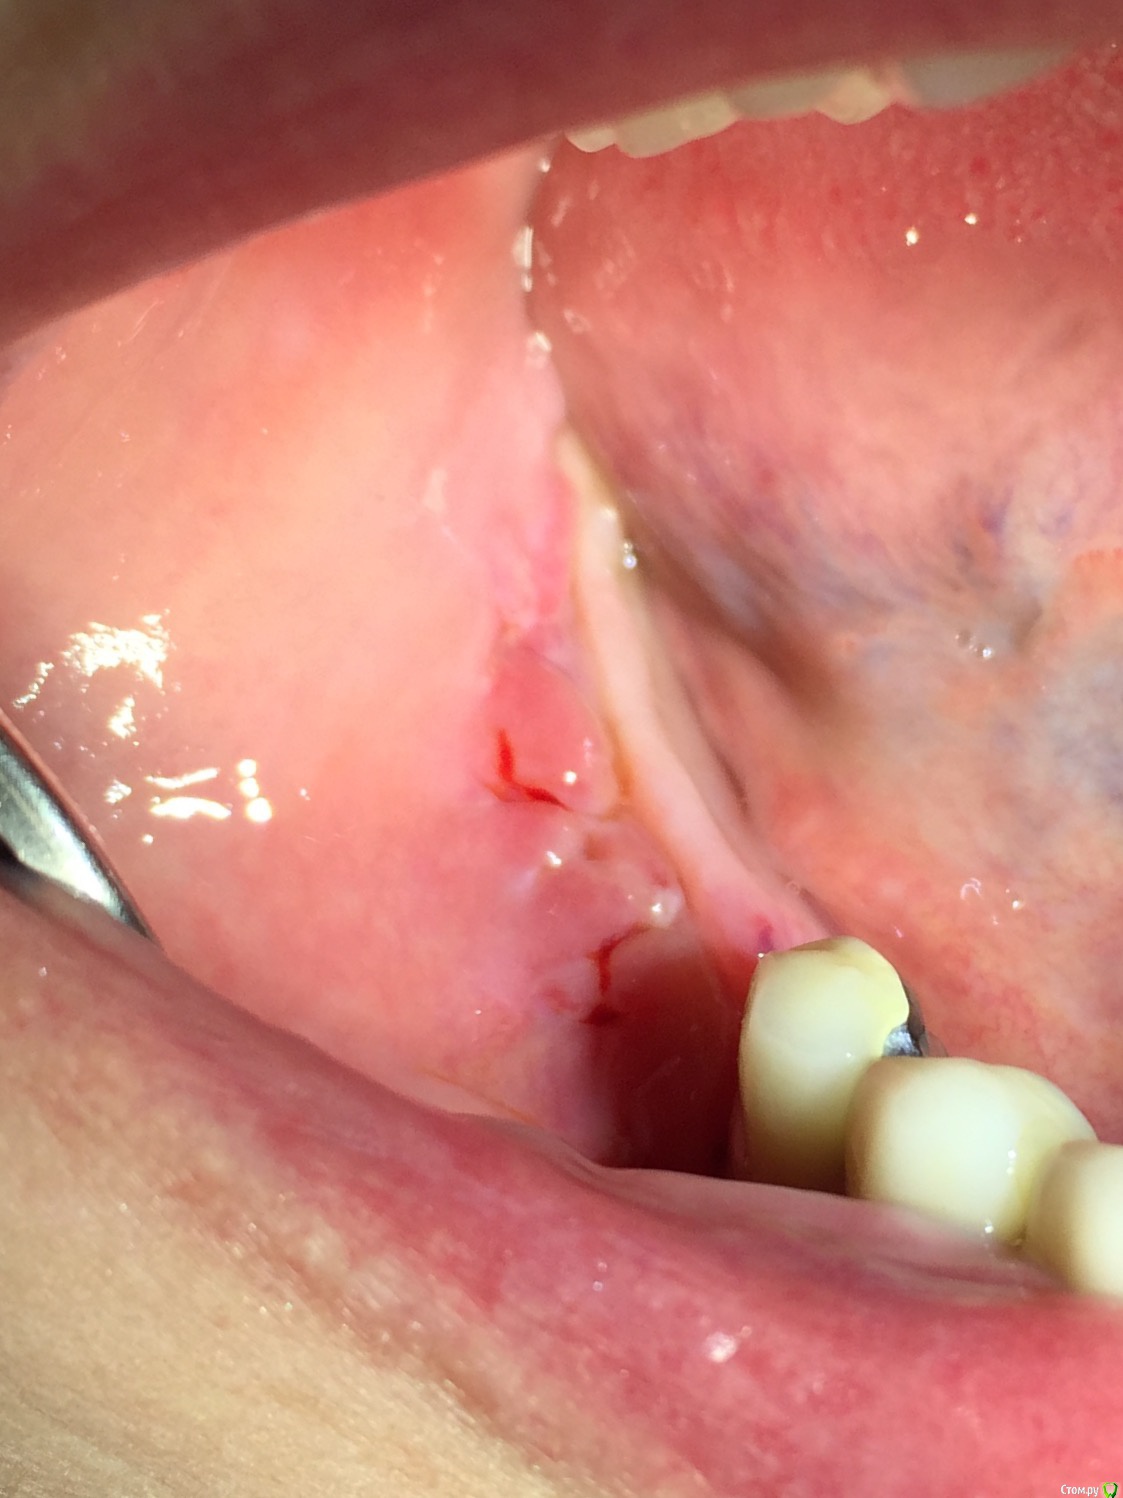

Глеб Митрофанов Опубликовано 5 ноября, 2015 Автор Поделиться Опубликовано 5 ноября, 2015 Этап снятия швов 4 Ссылка на комментарий